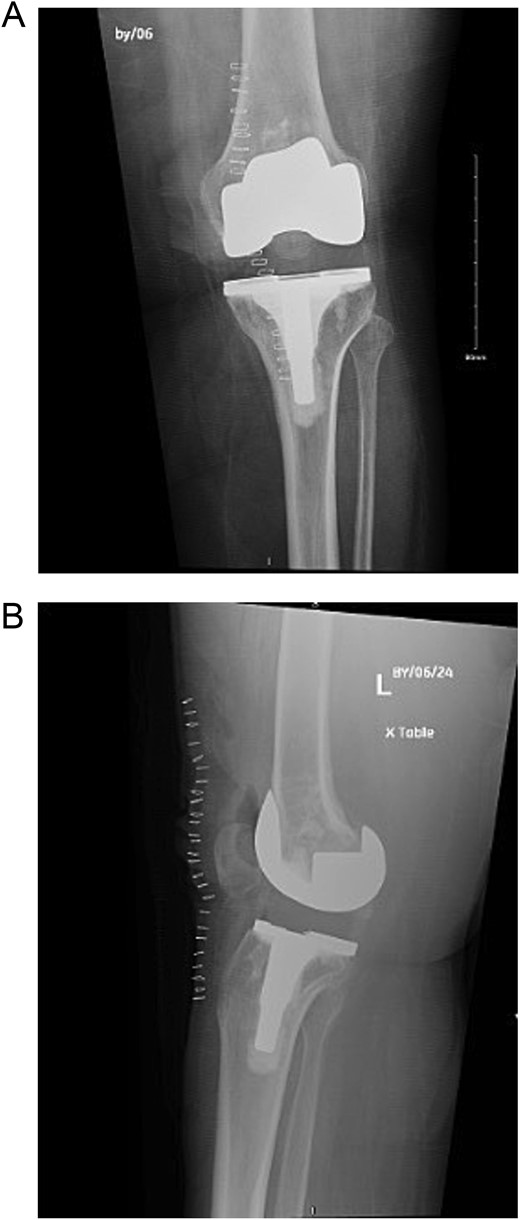

Post-operatively, the patient was seen by a physiotherapist and started immediate weight-bearing and range-of-motion exercises. She was seen in the clinic after 6 weeks, and reported significant relief of symptoms and satisfaction with the outcome (Fig. 6).

(A) Anteroposterior view of the left knee post revision and polyethylene replacement. (B) Lateral view of the left knee post revision and polyethylene replacement.